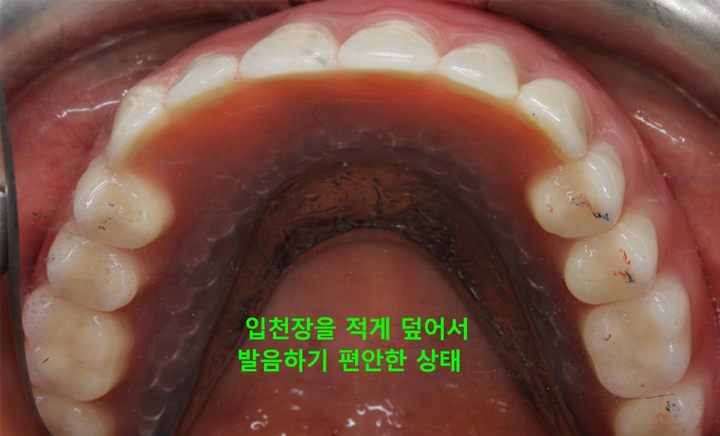

그리고 위턱의 틀니는 입천장이 있어 그나마 고정이 잘되지만 아래턱은 그런 구조물도 없는데다 혀가 자꾸 방해하기 때문에 고정하기가 쉽지 않아 틀니가 움직이는 불편함이 생깁니다. 이러한 틀니의 단점을 보완하고 틀니의 경제성과 임플란트의 기능성을 결합해 만들어진 것이 틀니 임플란트 입니다.